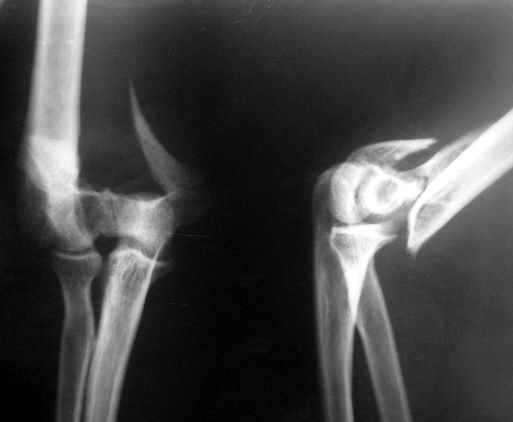

The recent x rays show established Non union with poor quality bone in the distal fragement. The joint is also appearing degenerate. In view of the multiple failed reconstructive surgeries, an Elbow replacement would seem reasonable.

Obviously there is no elbow joint...the options are few: (from the worst to the "best"...if any)